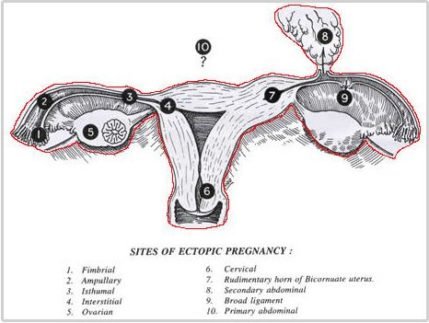

Ectopic pregnancy is the occurrence of a pregnancy in a site other than that of the uterine cavity. It is a serious condition and has to be treated promptly. It can occur in natural pregnancies and following procedures like Intra Uterine Insemination and Assisted Reproductive Technologies. It occurs as a consequence of current or previous tubal infection. The commonest portion of the tube where the pregnancy sits is in the ampulla. In very rare instances the ovary may be the seat of an ectopic. Sometimes it may also be due to transmigration of the embryo or egg to the opposite tube. The symptoms are a missed period or scanty flow on the expected date, giddiness and vomiting, most often accompanied by severe lower abdominal pain

The diagnosis is also confirmed with ultrasound and blood flow studies (Doppler) during which the sac may be visualized in the region of the adnexa close to ovary. The treatment may be medical with methotrexate (chemotherapeutic agent) given either as oral medication or an injectable, depending on the combined laboratory and clinical findings. If surgical intervention is decided upon then laparoscopic surgery will be performed in most patients who are hemodynamically stable. In cases where the patient presents late with the symptoms or the pregnancy has ruptured with bleeding into the abdomen laparotomy (10%) is performed.

The affected tube is most often if not always removed after examining the opposite tube and assessing the patient’s chances of future conception. Even with one healthy tube it is possible to conceive. In our experience removal of tube almost always reduced chances of recurrence and helped improve pregnancy rates by either trying for conception with the opposite tube or with ART.